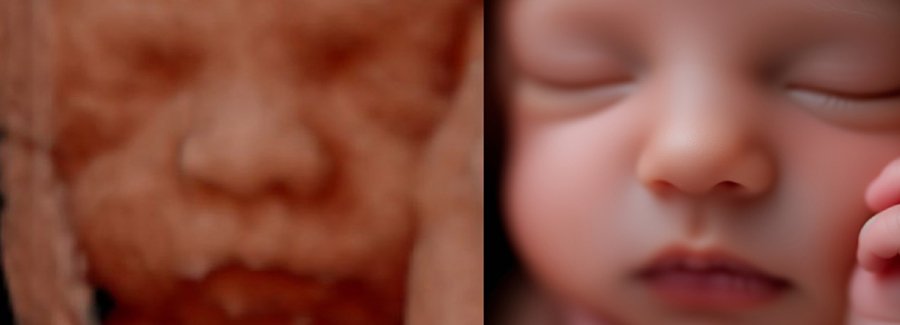

Often referred to as 5D, HD or FRV (fetal realistic view), 5D/HD is the newest development in pregnancy imaging. It captures and combines high definition volume data to create automated images with amazing color and clarity so you can see your baby as though you were looking from inside the womb.